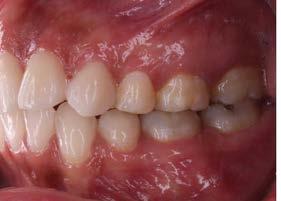

Se remitió a la especialidad en prostodoncia para valoración, indican abrir espacios en anteriores para su posterior restauración. Se retiró aparatología fija y se entregó retención con circunferenciales y fijo inferior (Figura 5).

Como resultado se logró cumplir con los objetivos establecidos al inicio del tratamiento, se liberó el apiñamiento y se logró hacer el cierre de la mordida anterior (Figura 6A), así como la

mejora en la estética de la sonrisa lo cual impacto positivamente en la autoestima de la paciente. Se estableció una clase I molar y canina, se obtuvo un correcto overjet y overbite, las líneas medias coincidieron y se establecieron correctas guías anteriores (Figura 6B).

Extraorales: Frente y perfil. B) Intraorales: oclusales, laterales y sobremordidas.

Figura 6. Fotografías finales. A)